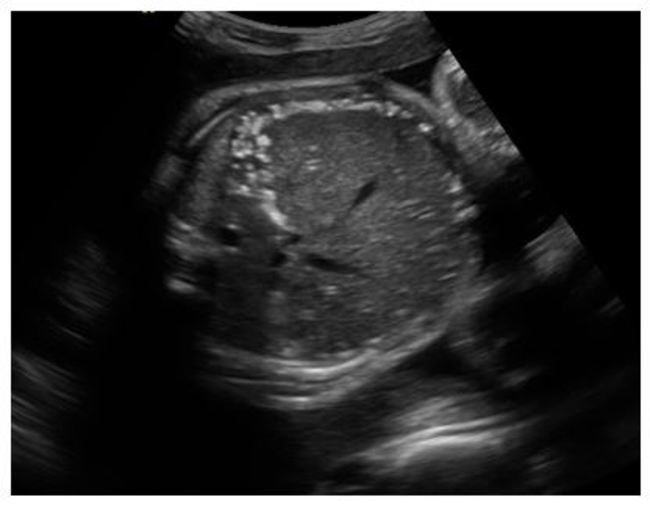

Meconium related process in cystic fibrosis.

What is meconium peritonitis?